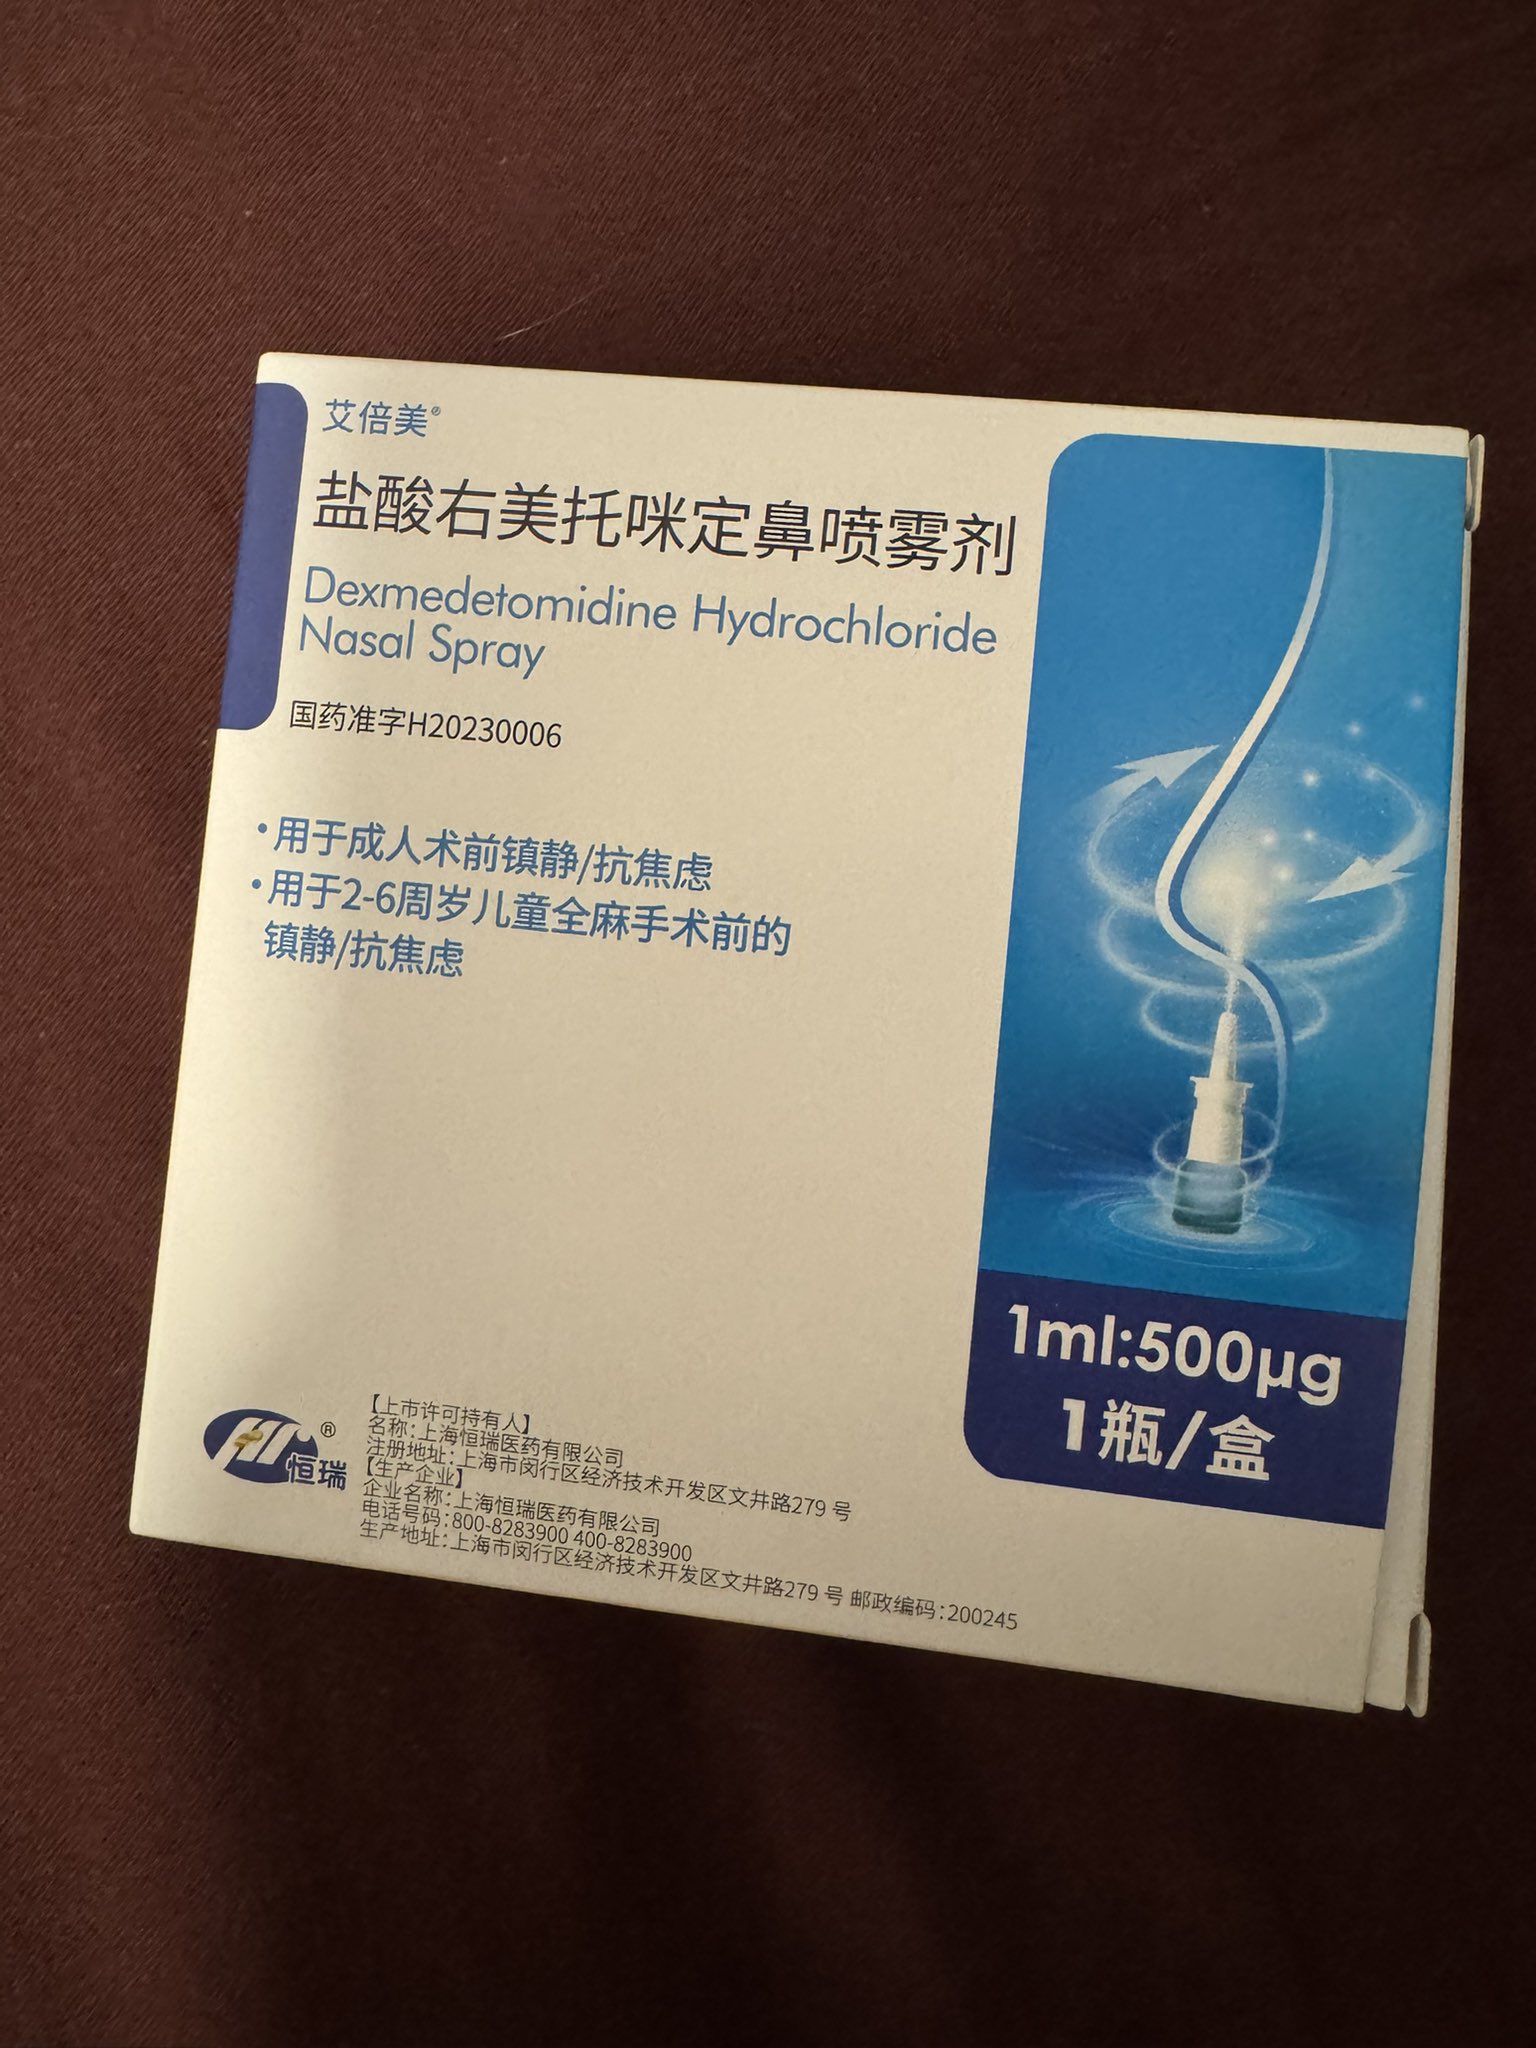

吃完唑吡坦会干一些难绷的事情,昨天睡不着疑似气急败坏了抽了0.5ml右美托咪定就是iv,还奇奇怪怪挑了个很痛的头静脉

你别说还扎得挺好的()按压时间估计也够,一点淤青也没有,不知道哪来的意志力 https://t.co/KxtfAUVSmb

@dDguwkiRkZcCSrt 怎么会()虽然右美托咪定舌下或鼻喷确实可以用于睡眠而且非常优秀接近自然睡眠,丙泊酚的话…嗯。工具箱+1,虽然这个浓度的安全窗口还是太大了而且半衰期短,所以配合另一种物质使用x